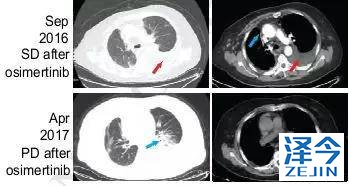

奥西替尼AZD9291治疗,病情稳定一段时间后,继续进展

因此,患者开始接受每日80mg的奥西替尼AZD9291治疗,患者在一个月内达到了病情稳定(SD),CA125水平迅速下降,经过8个月的无进展生存期,患者肺左下叶出现新的病灶,胸腔积液增多,病情发展。

布加替尼联合西妥昔单抗治疗,病情长期稳定控制

患者再次基因检测发现T790M-C797S顺式突变,因此在2017年7月开始联合使用布加替尼(90mg/日)和西妥昔单抗(600mg/月),治疗一个月时,患者的疲劳和呼吸困难明显改善,CA125水平明显下降,直到2018年4月病情一直稳定(PFS为9个月),除了轻度疲劳外无其他的不良反应。虽然在2018年4月患者出现脑转移灶,但在2018年9月,患者的胸部病灶依旧得到很好的控制。